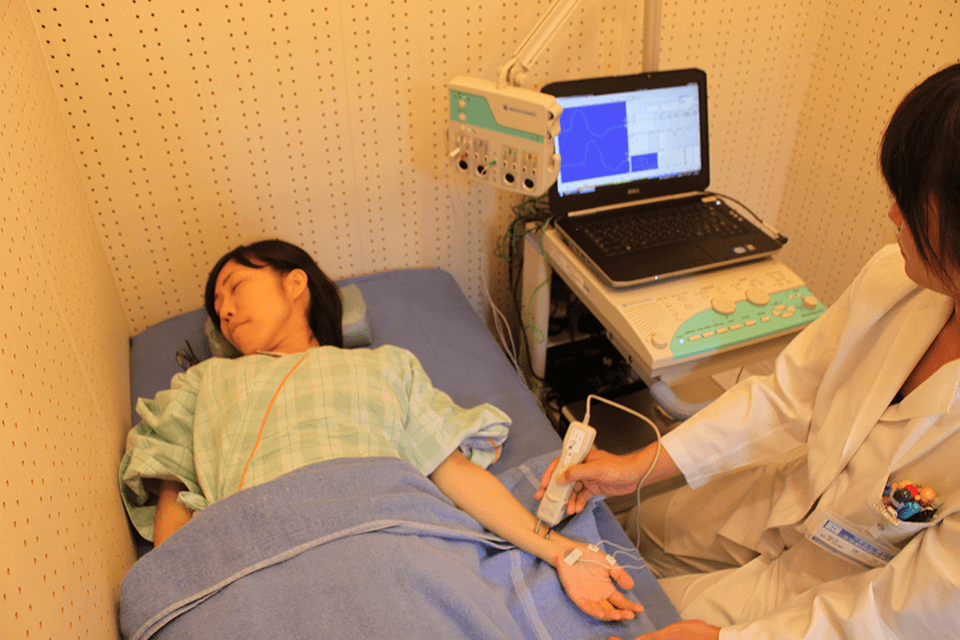

手や足に微弱な電流を流して末梢神経(運動神経・感覚神経)を刺激し、刺激が伝わる反応を手足に装着した電極から記録する検査です。

運動障害(動きづらさ・脱力)や知覚障害(感覚の鈍さ・しびれ・痛み)の原因が末梢神経障害によるものかどうか、またその障害部位や程度などを調べることができます。